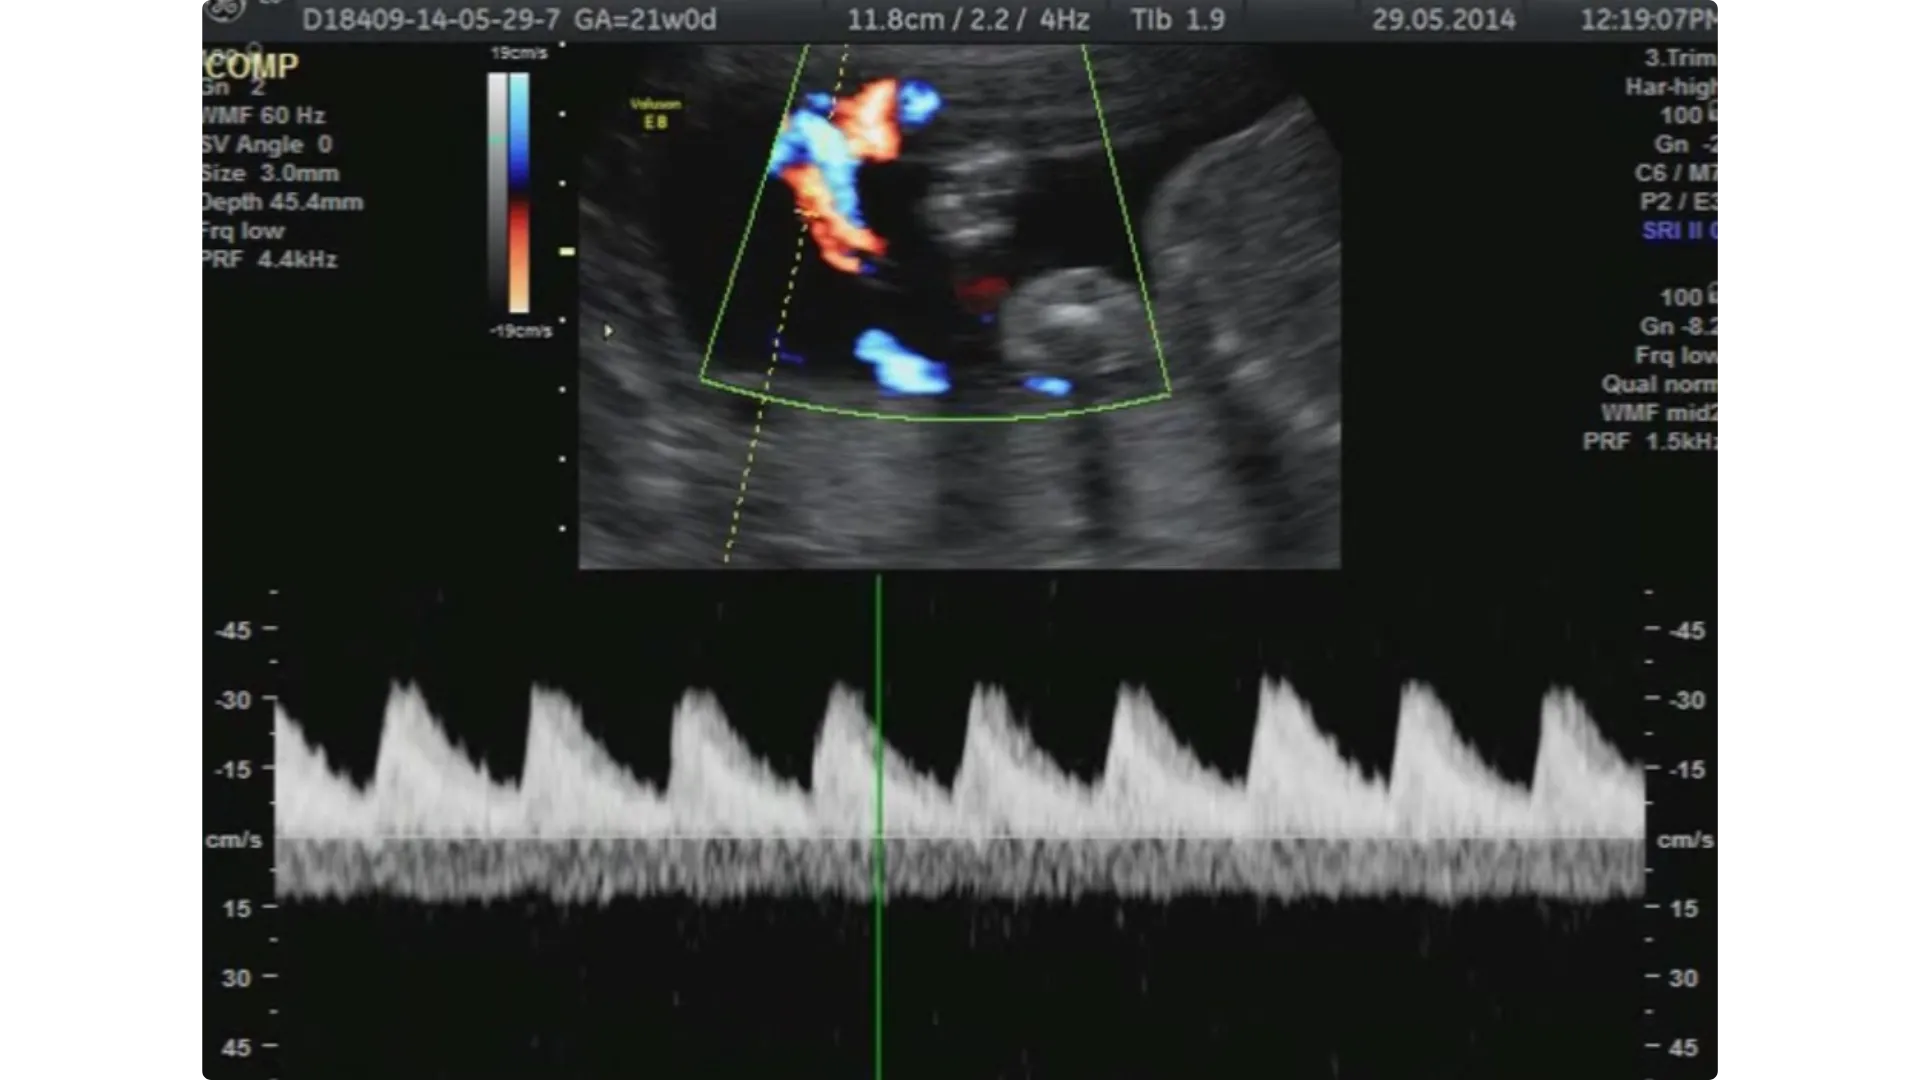

Ecocardiografia fetale

L'ecocardiografia è una semplice ecografia addominale effettuata intorno alla 20ª settimana mirata a studiare l’aspetto e il funzionamento del cuore del feto (affidabilità dell’80-90%).

Dovrebbe essere eseguita solo nel caso in cui ci sia un sospetto di malformazioni o malattie a carico del cuore e dei grandi vasi.

Flussimetria

Questa tecnica dovrebbe essere effettuata solo in caso di complicanze della gravidanza, come ad esempio la pressione alta, la preclampsia, il diabete gestazionale o ritardo nella crescita del feto.

Grazie alla flussimetria infatti è possibile sapere molte cose sullo stato di benessere del bimbo.

Fornisce informazioni utili circa l’elasticità di alcune arterie e il flusso sanguigno delle arterie uterine che portano il sangue dalla mamma alla placenta.

Attraverso l’analisi del flusso sanguigno del cordone ombelicale si valuta se il bambino riceve sufficienti quantità di ossigeno e di nutrienti di cui ha bisogno attraverso la placenta.

Solitamente la flussimetria fetale si esegue dalla 32ª settimana di gravidanza in poi, talvolta in concomitanza con l’ecografia del 3° trimestre.